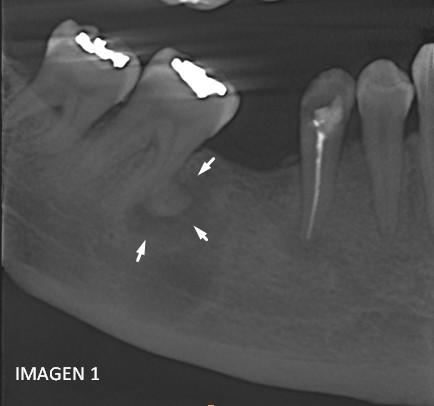

La presentación de casos radiográficos, permite la visualización de patologías que son muy difíciles de ver en la clínica, ya que muchos de ellos son hallazgos radiográficos. Además permite ver y refrescar clasificaciones y conceptos muchas veces estudiados. La presentación de los mismos no incluyen datos personales, mas que edad y sexo, que suelen ser importantes para ver la correlación entre la patología, su aparición o forma de presentación.

Esto también refleja las patologías que aquejan a los pacientes de nuestra región, y trata de ser un faro tanto para profesionales como alumnos que estudian dichas lesiones.

Dr CARNEIRO, Matias Reneé . (Odontólogo, Especialista por Imágenes Buco-Maxilo-Faciales)